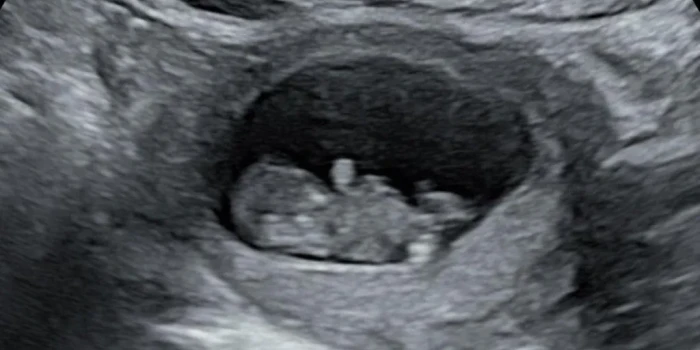

լկից հիշում է՝ երբ տեսավ իր հղիության թեստի երկուս գիծը, իր ու ամուսնու Մայքի սիրտը լցվեց հույսով։ Նրանք անվանեցին իրենց սպասվող բալիկին Ֆանտուս՝ մանկական կերպարի անունով, որը հաճախ տեսնում էին Դանիայում ընկերների մոտ այցելելիս։ Սակայն փոքրիկի առաջին կորստից հետո, երբ պարզվեց, որ 8 շաբաթականում նա մահացել է, իրենց աշխարհը փլուզվեց։ Հաջորդ հղիությունը որոշ ժամանակ հույս բերեց, բայց 20 շաբաթական ստուգումը ցույց տվեց՝ որդին՝ Հադսոնը, ունեցել է ձախ սրտի ծանր բնածին խնդիր և ծնվել է մահացած՝ 22 շաբաթականում։ Սոցիալական ցանցերի միջոցով նրանք փնտրում էին աջակցություն, բայց նաև շարունակ հանդիպում էին բալիկներին վերաբերող գովազդների։ «Հղիության հավելվածները շարունակում են տեղեկացնել կարևոր փուլերի մասին, խանութները առաջարկում են զեղչեր այն ամենի համար, ինչ մեզ երբեք պետք չի լինելու», — ասում է Ռիանոնը։ Սեպտեմբերի վերջում Meta-ն հայտարարեց, որ Միացյալ Թագավորությունում մտնում է բաժանորդագրային ծառայություն՝ գովազդներ չցուցադրելու համար, ամսական 2.99 ֆունտով։ Սակայն Ռիանոնը կարծում է, որ դա խնդիր չի լուծի։ Այնուհետև պատմություններ են, ինչպիսիք են Հեյլի Դոուի և նրա զուգընկեր Աंथոնի մոտ. IVF փորձերի անհաջողություններից հետո նրանք սպասում էին երկվորյակների, բայց արագորեն կորստի սարսափ ապրեցին։ Սոցիալական ցանցերում աջակցություն գտնելը խանգարող գովազդների պատճառով դարձավ դժվար։ Meta-ի նախկին աշխատակից Արթուրո Բեխարը նշում է՝ «mark as spam» կոճակը հաճախ չէր աշխատում. համակարգը ոչնչով չկարողացավ պաշտպանել օգտատերերին։ Նա նաև վկայություն է տվել ԱՄՆ Կոնգրեսում՝ Meta-ի անվտանգության թերությունների մասին։ Meta-ի ներկայացուցիչը պատասխանեց. «Մենք լուրջ ենք վերաբերվում այս մտահոգություններին և շարունակում բարելավել գովազդների ճշգրտությունը։ Մենք հորդորում ենք մարդկանց բացառել որոշ կատեգորիաներ, երբ դա անհրաժեշտ է»։ Հոդվածում տված պատմությունները վկայում են, թե ինչպես տեխնոլոգիաները հաճախ անզգայունորեն վերաբերվում են կորստի ցավին, և որքան դժվար է օգտատերերի համար պաշտպանել իրենց հոգեկան առողջությունը, երբ բախվում են անմեղ, բայց ցավալի գովազդների։ Եթե այս հոդվածում ներկայացված խնդիրներից որևէ մեկը վերաբերում է ձեզ, կարող եք այցելել BBC Action Line՝ օգնություն ստանալու համար: